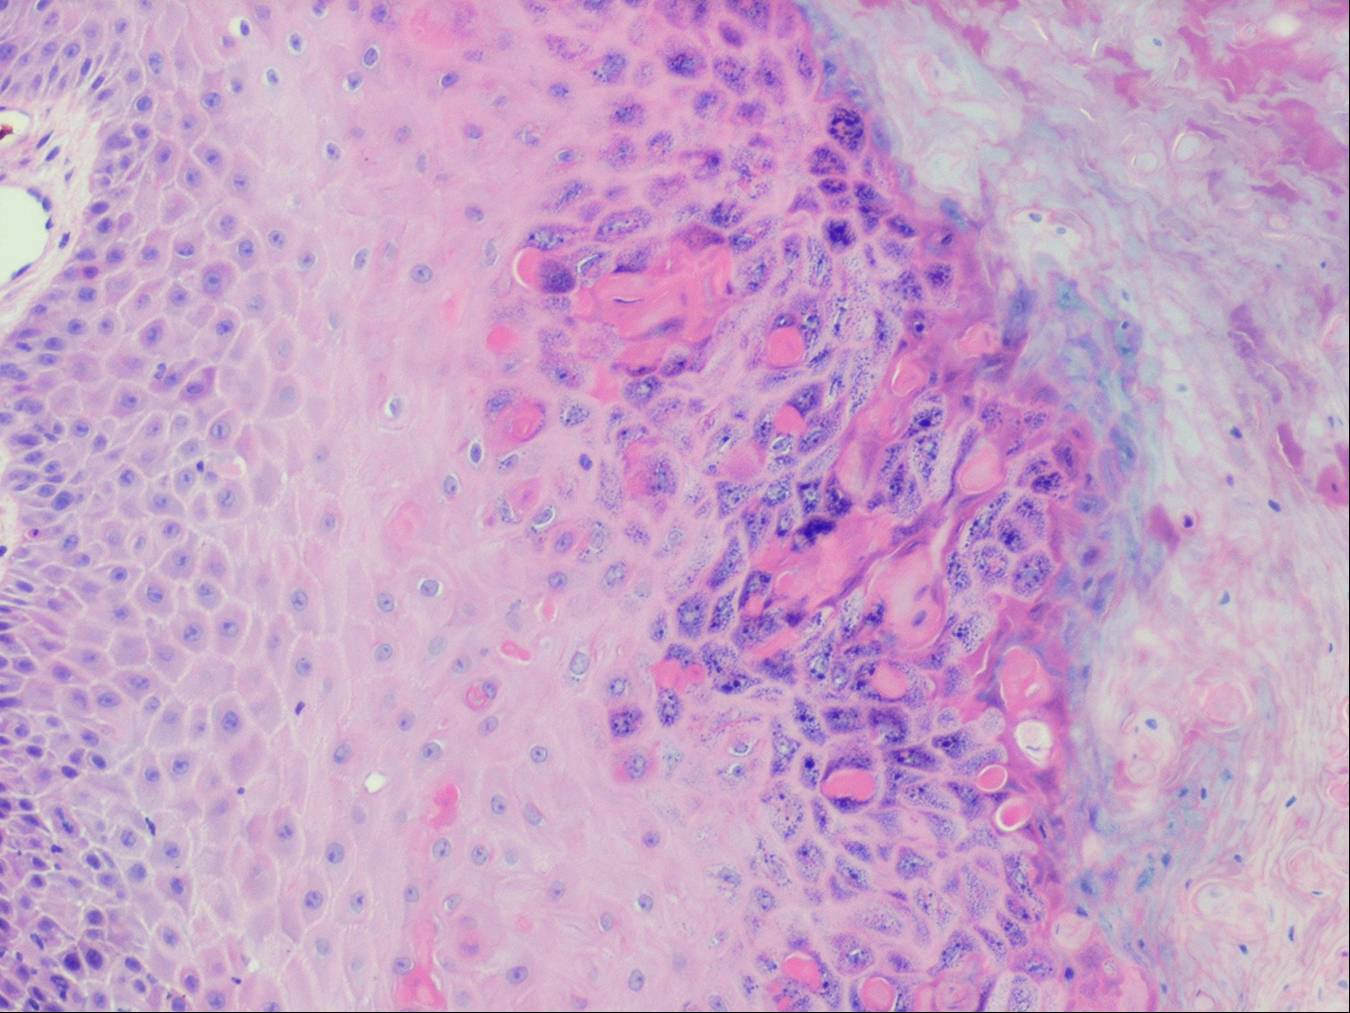

The alterations in the second stage consist of acanthosis, irregular papillomatosis, and hyperkeratosis. Intraepidermal keratinization, consisting of whorls of keratinocytes and of scattered dyskeratotic cells, is often more pronounced than in the first stage. The basal cells show vacuolization and a decrease in their melanin content. The dermis shows a mild, chronic inflammatory infiltrate intermingled with melano-phages. This infiltrate extends into the epidermis in many places.